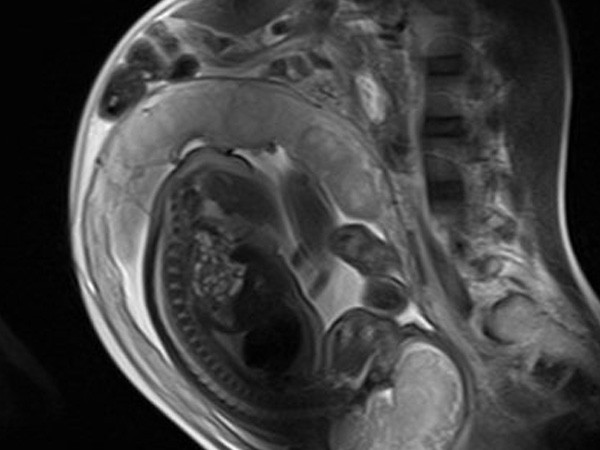

Washington: A team of researchers recently found that a powerful MRI technique can detect early signs of abnormalities in fetuses due to congenital heart disease (CHD) during the second trimester of pregnancy.

According to researchers, the findings demonstrate that placental dysfunction due to CHD can be apparent as early as in the second trimester of pregnancy using this imaging technology.

The researchers used velocity-selective arterial spin labeling (VSASL), a powerful MRI technique, that directly measures the rate of delivery of arterial blood to organs like the brain.

The team led by Catherine Limperopoulos, examined 48 pregnant women who underwent at least one fetal magnetic resonance imaging (MRI) session during their second or third trimester of pregnancy.

About 31 women were healthy volunteers whose mean gestational age was 30 weeks (range: 21 to 39 gestational weeks) and 17 were pregnant with fetuses diagnosed with CHD whose mean gestational age was 32 weeks.